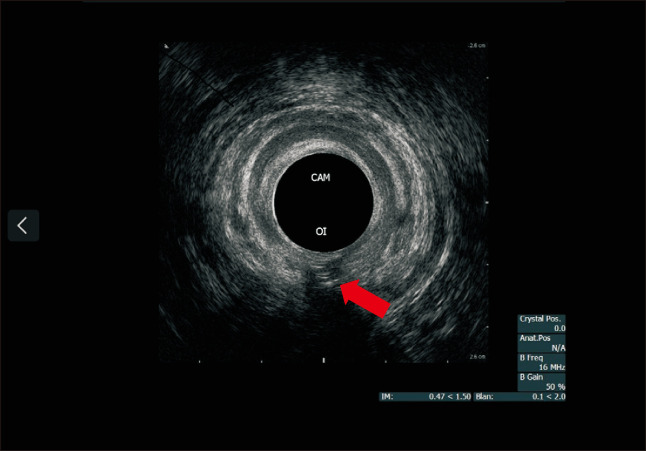

Three-dimensional Anorectal Manometry in a Patient With Passive Fecal Incontinence and a History of Complex Perianal Fistula Treated With Fistulectomy.

一名被动性大便失禁患者的三维肛门直肠测压法以及瘘管切除术治疗复杂性肛周瘘的病史。